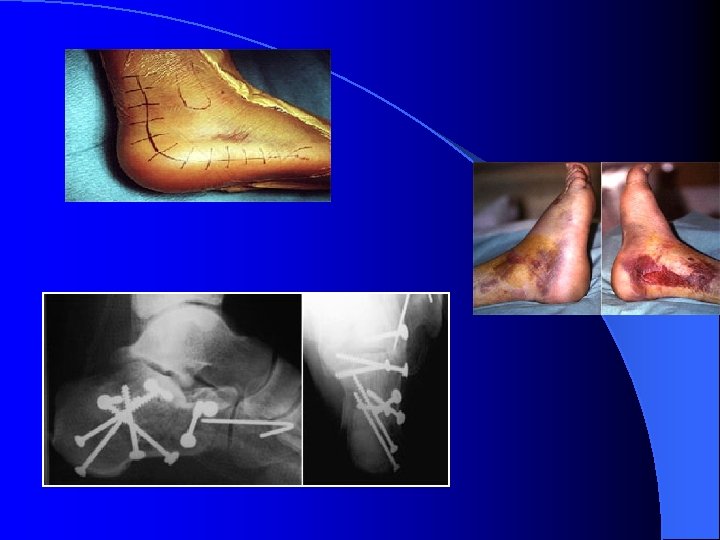

Calcaneus l l l l l Chute hauteur ++ Déplacée LESIONS CUTANEES Articulaire ++ Sous –talienne ++ Forme globale Valgus /Varus Aplatissement AP TDM /IRM

luxation articulation de Chopart l luxation de l'articulation de CHOPART, entre scaphoïde et cuboïde d'une part et talus et calcaneus, d'autre part. l fractures associées au niveau du scaphoïde et du cuboïde. réduction doit être alors parfaite ( arthrose secondaire ). l La réduction manuelle est possible , le plus souvent , un embrochage percutané est souvent réalisé cependant. immobilisation de 6 à 8 semaines

luxation articulation de Chopart